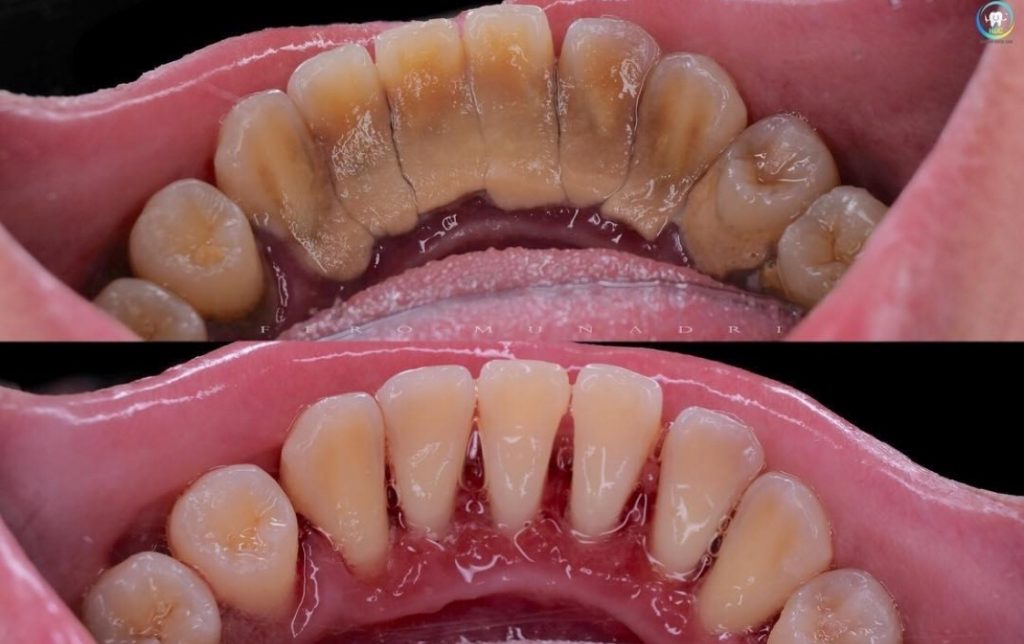

Diş temizliği ile bakteri plakları ve diş taşları uzaklaştırılır, yani bu işlem diş etinin tedavisidir. Bu yüzden “diş temizleme zararlı mıdır?” diye sorulan soruların aslında hiçbir mantığı yoktur. Bilakis diş temizleme son derece sağlıklı bir tedavidir ve etkisi anında görülür.

Diş taşlarının uzun süre temizlenmemesi nedeniyle diş etleri çekilmiş bir hastanın diş taşlarını temizlediğimizde diş kökleri açığa çıkar. Hasta, diş taşlarını temizlettiği için diş köklerinin açığa çıktığını düşünebilir.

Ancak asıl sebep: Belirttiğimiz gibi kötü ağız hijyeninden kaynaklanan diş eti çekilmeleridir, yapılan diş temizliğinden dolayı değildir!

Gerçek şu ki, diş taşları yıllardır çekilmiş olan diş etini örtüyordu. Temizlik sonrası gerçek durum ortaya çıkmıştır.